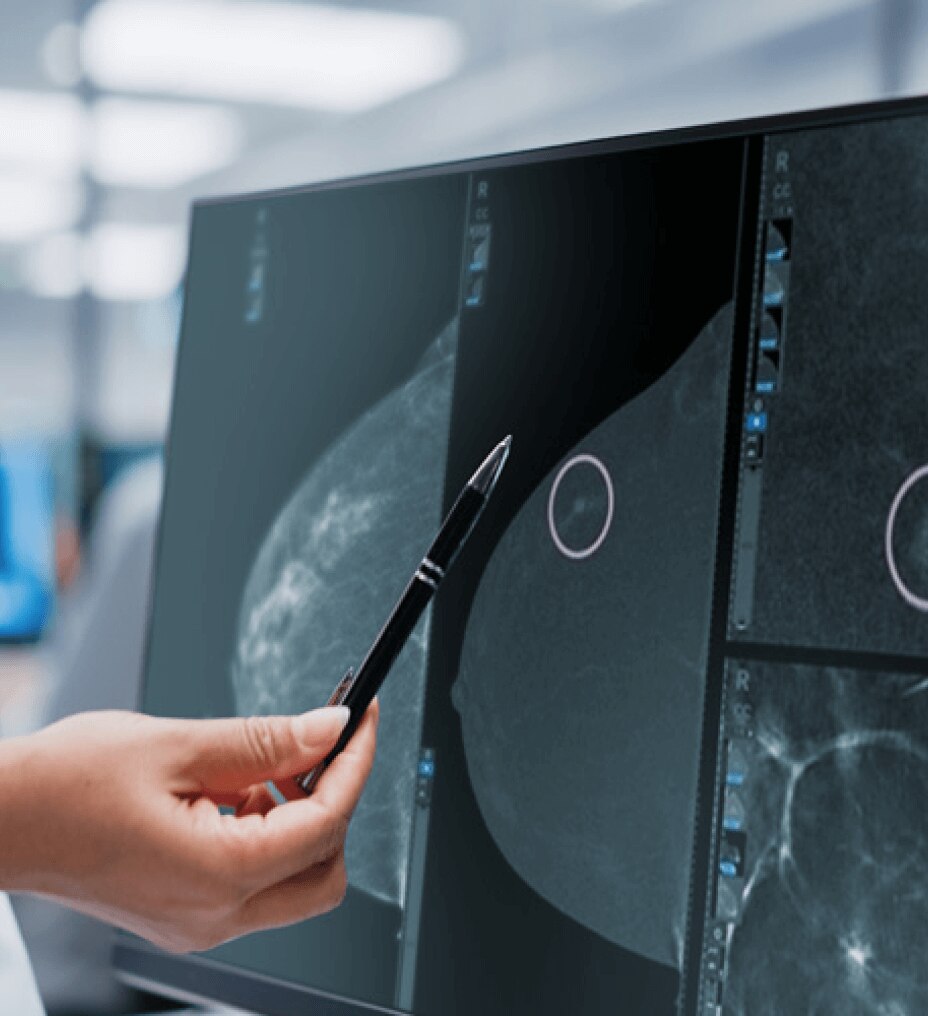

En zorlu departman programlarını bile SIGNA™ Hero ile verimli hale getirin. AIR™ Koiller ve AIR™ Recon DL, genel klinik pratiğin bir parçası olarak meme ve prostat kanseri incelemesi gibi alanlarda uçtan uca klinik çözümlere sahip olmanızı sağlar.